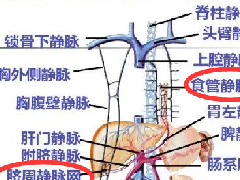

| 类 型 | 影像表现 | 小 结 |

| 脂肪浸润(图1〜图 3) | 肝脏密度弥漫性减低。在肝脏脂肪变的低密度背景下,门静脉表现为高密度结构(平扫时正常门静脉呈低密度)。 | 由于三酰甘油过度沉积所致,见于肝硬化或其他肝脏疾病。正常肝脏平均CT值不低于脾脏,肝脏脂肪 浸润时CT密度较低。肝硬化引起脂肪浸润,伴有肝右叶萎缩,尾状叶体积增大。 |

图1肝硬化患者的肝内脂肪浸润

图2肝硬化患者的肝内斑片状脂肪浸润

图3肝硬化再生结节